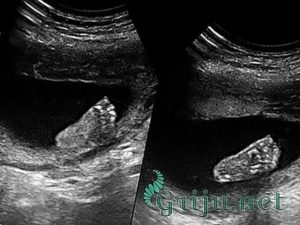

Совет! При проведении ультразвукового исследования могут быть измерены копчиково-теменные размеры плода, на 11 неделе беременности этот показатель составляет около 5 см. Но поскольку рост и развитие ребенка на этом этапе происходит стремительно, то уже через пару недель размеры вашего малыша увеличатся вдвое.

В первый раз рекомендуется проходить скрининг в период с 11 по 16 неделю. Причем врачи рекомендуют пройти это обследование, пока не началась 12 неделя беременности. Дело в том, что в это время хорошо видна воротниковая зона плода, а измерение этой части тела позволяет своевременно выявить наличие риска развития у плода синдрома Дауна.

Будущие мамы должны понимать, что при проведении УЗИ на 11 неделе беременности диагноз не ставят. Проведение скрининга позволяет определить степень риска. То есть, если будут получены результаты, не соответствующие норам, то будущей маме порекомендуют пройти дополнительные экспертные УЗИ и проконсультироваться у врача-генетика.

УЗИ

Обычно на 11 неделе беременности УЗИ пока еще не требуется. Но, в отдельных случаях – для подтверждения нормального протекания беременности, оценки развития плода и исключения возможных нарушений в развитии малыша или плаценты, для диагностики состояния матери при наличии ноющих болей в животе – женщину по решению врача могут направить на внеплановое ультразвуковое исследование.

Переживать будущей роженице не стоит – специалисты уверяют, что УЗИ является абсолютно безопасным методом обследования, а некоторых и вовсе обследуют при помощи ультразвука многим раньше, на 10, и даже на 9 неделе беременности.

Во время УЗИ врач сможет прослушать сердцебиение плода, и, исходя из полученных данных, сделать выводы о его развитии.

Также ультразвуковое исследование позволит врачу оценить размеры и состояние матки, установить место крепления плода и расположение плаценты, количество и качество околоплодных вод.